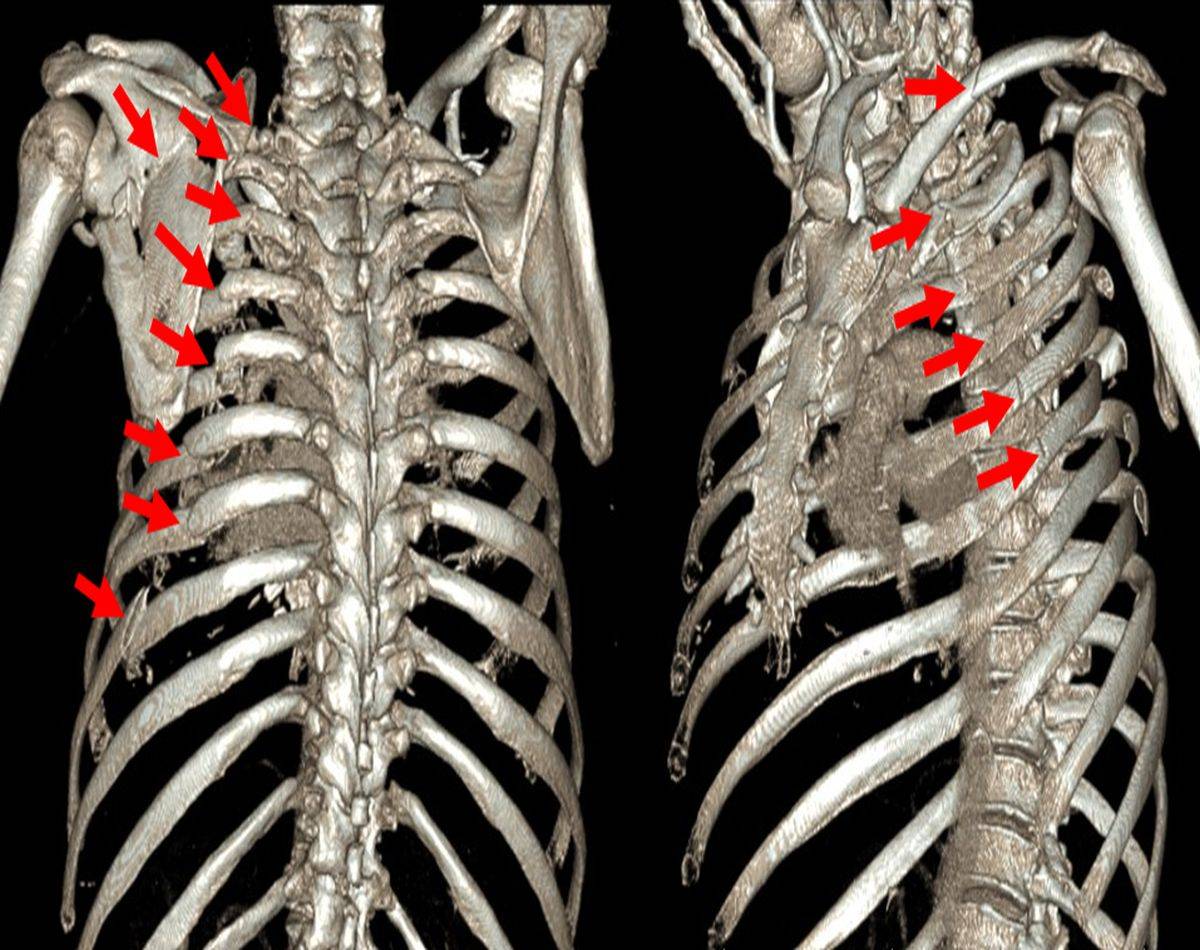

胸片可见左侧锁骨骨折,左侧第四肋骨骨皮质皱褶,易漏诊。 ct证实为左侧第二四五肋骨骨折。细微骨折,裂纹骨折,对位良好的骨折,在x片上极其容易漏诊。 病例2 女,79岁,外伤。 胸部正位双侧肋骨未见明显错位骨折,主动脉硬化。 ct可见右侧第五前肋骨折。Hello 醫師台灣 本內容經醫學專家審稿 肋骨とは胸の内臓を覆い、胸の臓器を外力から守る役割を担っている骨です。 肋骨骨折は全骨折の 10% の割合で起き、肋骨骨折の起きやすい部位は5〜8本目の肋骨が多い傾向にありま

胸部正位双侧肋骨未见明显错位骨折,主动脉硬化。 ct可见右侧第五前肋骨折。老年人,肺纹理粗乱,前肋靠近胸骨,重叠较多,易漏诊。 如何避免肋骨骨折的漏诊? 1询问患者有无受伤病史,车祸,摔伤,撞伤等。

那些年 你漏診過的肋骨骨折 醫學界影像診斷與介入頻道 微文庫

那些年 你漏诊过的肋骨骨折 壹读